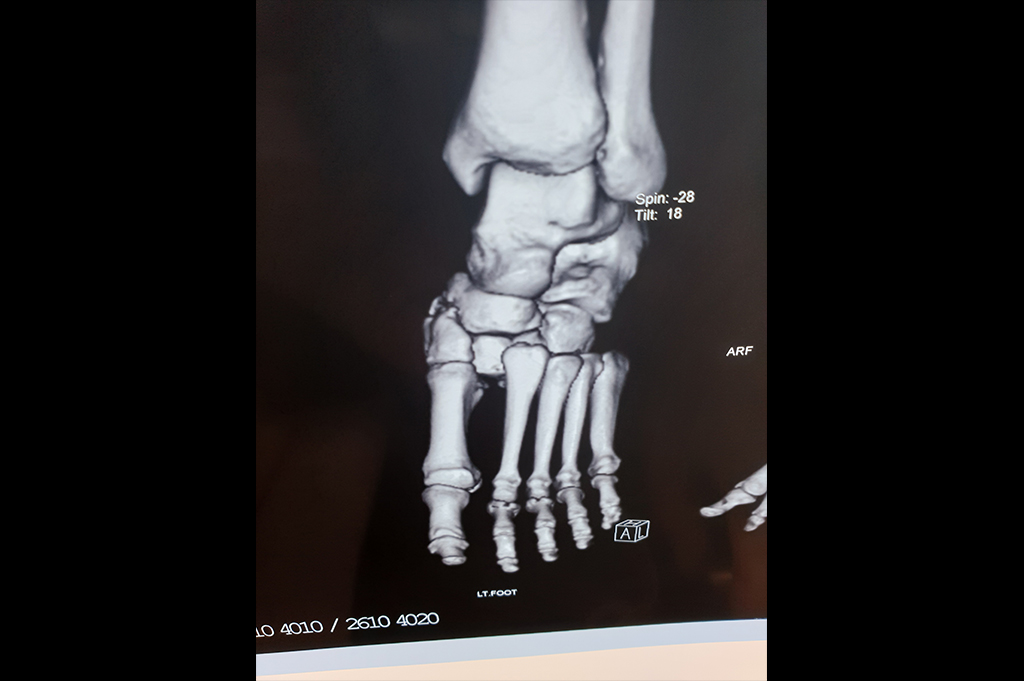

Metarsals with dislocations Lisfranc